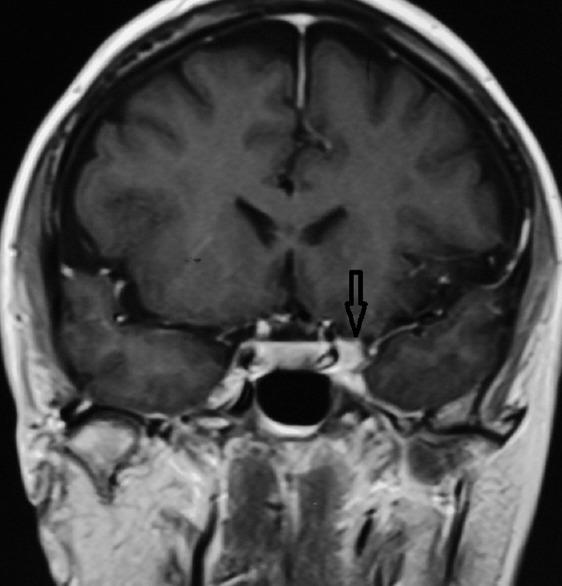

We describe a case of THS in a 55-year-old woman presenting with left painful opthalmoplegia that was diagnosed by CISS MRI. Patient responded to steroid treatment and the lesion resolved.

Imaging with MRI can help in making the diagnosis of THS by demonstrating an enhancing soft tissue lesion in the cavernous sinus and orbital apex resolving with steroids. CISS MRI is a sensitive sequence for diagnosis and follow-up imaging in THS.

我们描述了一例55岁女性的THS病例,该患者表现为左侧疼痛性眼肌麻痹,通过CISS磁共振成像得以诊断。患者对类固醇治疗有反应,病变消退。

磁共振成像有助于诊断THS,可显示海绵窦和眶尖有强化的软组织病变,且病变在类固醇治疗后消退。CISS磁共振成像是THS诊断及随访成像的敏感序列。